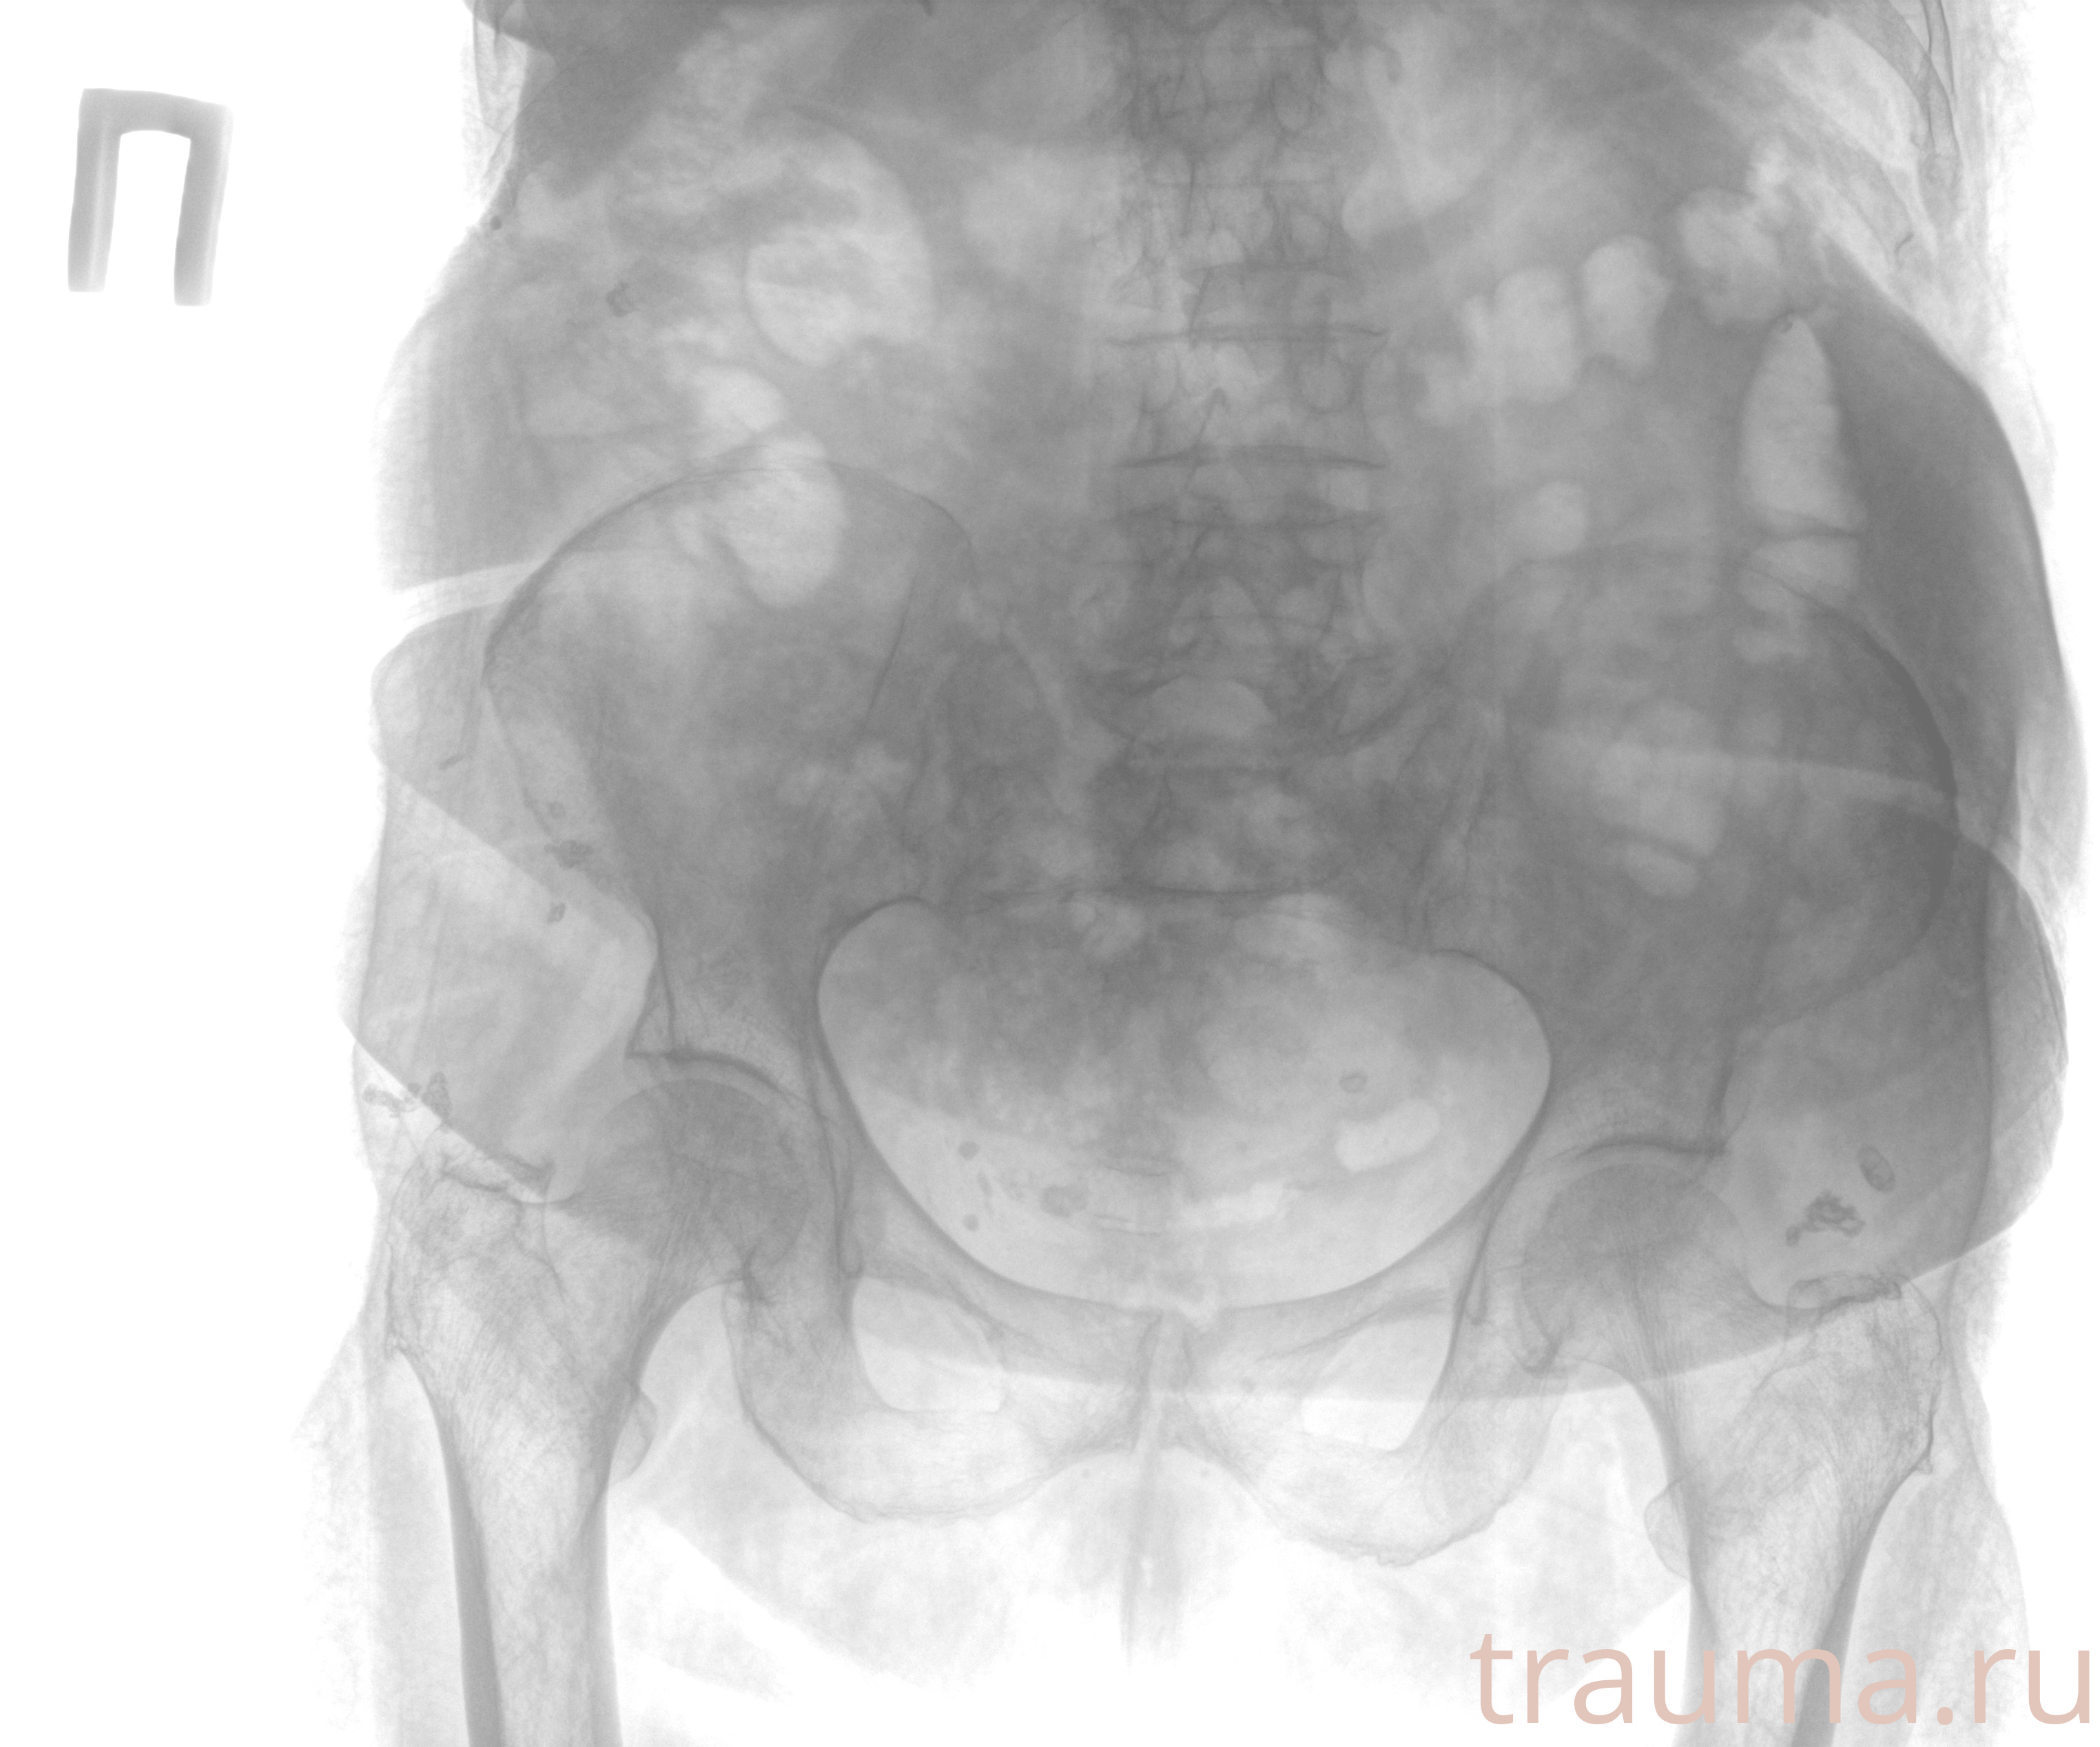

Рентген на дому: по вашему адресу приезжает врач-рентгенолог, травматолог-ортопед с мобильным рентгеновским аппаратом, проводит диагностику травмы или заболевания, делает необходимые рентгенограммы, дает рекомендации по дальнейшему лечению. Получить качественные снимки в домашних условиях возможно благодаря уникальной методике, разработанной МосРентген Центром для института  Склифосовского

при переломе шейки бедра и пневмонии от компании МосРентген Центр - партнера Института имени Склифосовского